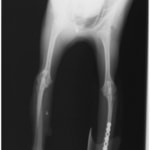

ペルシャ猫 11ヶ月齢 雄

他院にて左大腿骨遠位の成長板骨折(salter-harrisⅠ型)が認められており、治療相談を目的として来院。当院にて、キルシュナーワイヤーを用いたピンニングにより骨折部位の整復を行いました。術後の経過は良好で、現在も経過観察中です。

術前レントゲン